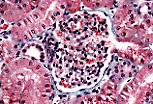

马尔皮基氏小体由一个毛细血管丛(肾小球)及其包裹的囊(鲍曼氏囊)组成。鲍曼氏囊包括一个壁层和一个紧贴毛细血管的脏层。两层之间有一个空间,即肾小球囊腔。

可以形象地理解为,毛细血管丛像拳头一样塞入鲍曼氏囊中。 |

毛细血管丛构成一个

奇网毛细血管

,因为它是在两条小动脉(入球小动脉和出球小动脉)之间发育的。

小动脉进出区域构成肾小球的血管极。在常规染色下,无法区分入球小动脉和出球小动脉。 |